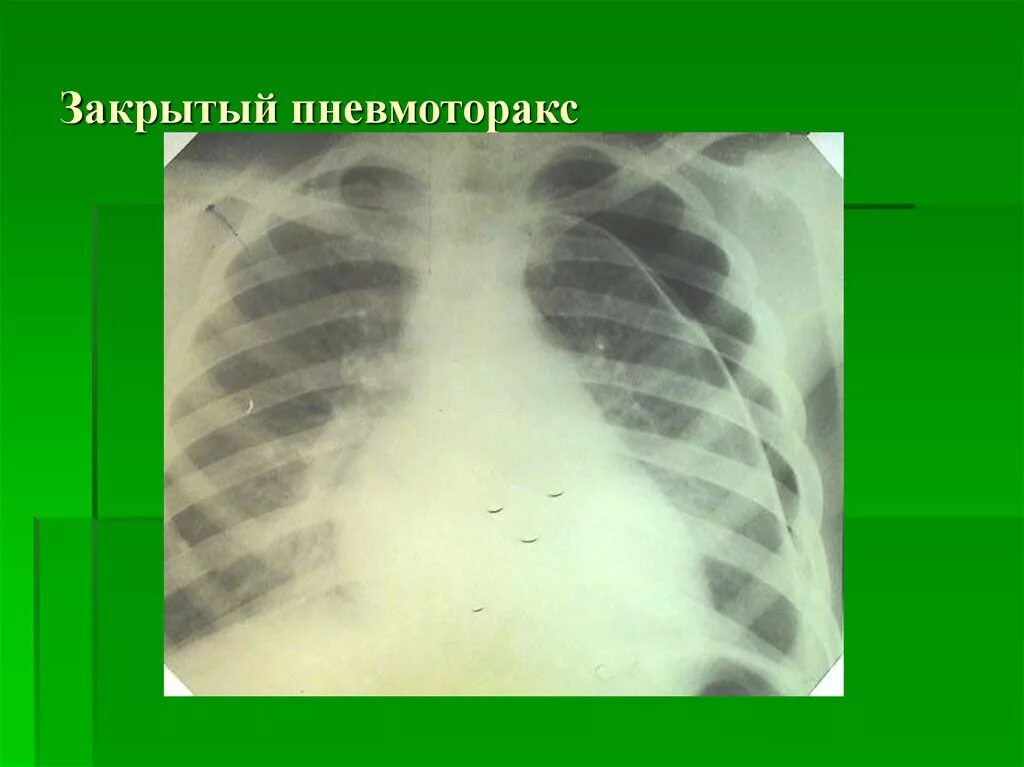

Коллабированное легкое при пневмотораксе